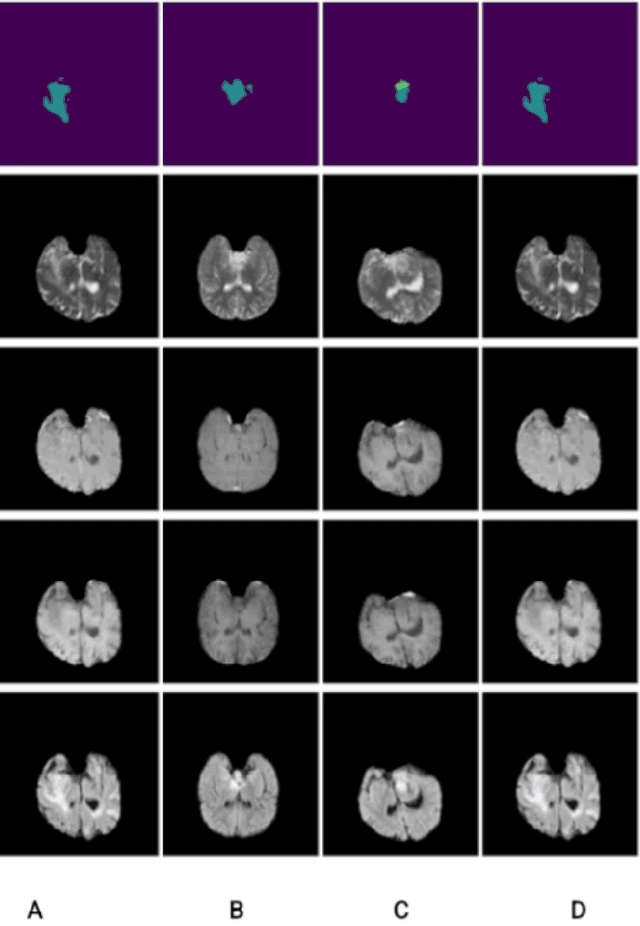

Abstract:Segmentation of brain tumors is a critical step in treatment planning, yet manual segmentation is both time-consuming and subjective, relying heavily on the expertise of radiologists. In Sub-Saharan Africa, this challenge is magnified by overburdened medical systems and limited access to advanced imaging modalities and expert radiologists. Automating brain tumor segmentation using deep learning offers a promising solution. Convolutional Neural Networks (CNNs), especially the U-Net architecture, have shown significant potential. However, a major challenge remains: achieving generalizability across different datasets. This study addresses this gap by developing a deep learning ensemble that integrates UNet3D, V-Net, and MSA-VNet models for the semantic segmentation of gliomas. By initially training on the BraTS-GLI dataset and fine-tuning with the BraTS-SSA dataset, we enhance model performance. Our ensemble approach significantly outperforms individual models, achieving DICE scores of 0.8358 for Tumor Core, 0.8521 for Whole Tumor, and 0.8167 for Enhancing Tumor. These results underscore the potential of ensemble methods in improving the accuracy and reliability of automated brain tumor segmentation, particularly in resource-limited settings.

Abstract:In Sub-Saharan Africa (SSA), the utilization of lower-quality Magnetic Resonance Imaging (MRI) technology raises questions about the applicability of machine learning methods for clinical tasks. This study aims to provide a robust deep learning-based brain tumor segmentation (BraTS) method tailored for the SSA population using a threefold approach. Firstly, the impact of domain shift from the SSA training data on model efficacy was examined, revealing no significant effect. Secondly, a comparative analysis of 3D and 2D full-resolution models using the nnU-Net framework indicates similar performance of both the models trained for 300 epochs achieving a five-fold cross-validation score of 0.93. Lastly, addressing the performance gap observed in SSA validation as opposed to the relatively larger BraTS glioma (GLI) validation set, two strategies are proposed: fine-tuning SSA cases using the GLI+SSA best-pretrained 2D fullres model at 300 epochs, and introducing a novel neural style transfer-based data augmentation technique for the SSA cases. This investigation underscores the potential of enhancing brain tumor prediction within SSA's unique healthcare landscape.

Abstract:Gliomas, the most prevalent primary brain tumors, require precise segmentation for diagnosis and treatment planning. However, this task poses significant challenges, particularly in the African population, were limited access to high-quality imaging data hampers algorithm performance. In this study, we propose an innovative approach combining the Segment Anything Model (SAM) and a voting network for multi-modal glioma segmentation. By fine-tuning SAM with bounding box-guided prompts (SAMBA), we adapt the model to the complexities of African datasets. Our ensemble strategy, utilizing multiple modalities and views, produces a robust consensus segmentation, addressing intra-tumoral heterogeneity. Although the low quality of scans presents difficulties, our methodology has the potential to profoundly impact clinical practice in resource-limited settings such as Africa, improving treatment decisions and advancing neuro-oncology research. Furthermore, successful application to other brain tumor types and lesions in the future holds promise for a broader transformation in neurological imaging, improving healthcare outcomes across all settings. This study was conducted on the Brain Tumor Segmentation (BraTS) Challenge Africa (BraTS-Africa) dataset, which provides a valuable resource for addressing challenges specific to resource-limited settings, particularly the African population, and facilitating the development of effective and more generalizable segmentation algorithms. To illustrate our approach's potential, our experiments on the BraTS-Africa dataset yielded compelling results, with SAM attaining a Dice coefficient of 86.6 for binary segmentation and 60.4 for multi-class segmentation.